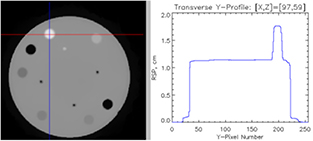

Download figure:

Standard image High-resolution imageAnother proton radiography instrument development effort that is more recent than the PSI effort is the advanced quality assurance project (AQUA) at the TERA foundation [90, 91]. The tracking is based on  GEM detectors [92], a pixelated detector that operates with gain from electron multiplication by a gas, which are placed only immediately in front of the range detector. Addition of another set in front of the phantom is being investigated, but the team prefers use of the beam scanning system to define the incoming proton trajectory, in order to enhance the portability of the system within a clinic. The range detector is a stack of 48 three-millimetre-thick (not including wrapping) scintillator planes, each coupled by a wave-shifting fiber to an SiPM. The signals are individually digitized by 12-bit pipelined ADCs, and the data acquisition system can handle a throughput of about a million events per second. Up to this time, results have only been published from the 10 cm square prototype system [91], which had a similar construction but a different electronic readout system. The large 30 cm square system was ready for testing as of March 2015, but no published results have yet appeared.

GEM detectors [92], a pixelated detector that operates with gain from electron multiplication by a gas, which are placed only immediately in front of the range detector. Addition of another set in front of the phantom is being investigated, but the team prefers use of the beam scanning system to define the incoming proton trajectory, in order to enhance the portability of the system within a clinic. The range detector is a stack of 48 three-millimetre-thick (not including wrapping) scintillator planes, each coupled by a wave-shifting fiber to an SiPM. The signals are individually digitized by 12-bit pipelined ADCs, and the data acquisition system can handle a throughput of about a million events per second. Up to this time, results have only been published from the 10 cm square prototype system [91], which had a similar construction but a different electronic readout system. The large 30 cm square system was ready for testing as of March 2015, but no published results have yet appeared.

With the smaller system the proton range was measured event by event in two ways: by using a simple threshold to locate the last scintillator hit and by detailed fitting of the ADC signals to a function shaped similar to the expected Bragg peak. Both methods gave the same range precision, limited by range straggling as well as measurement errors, suggesting that the readout could be simplified by eliminating the ADCs. From analysis of data taken with a 2 cm thick acrylic phantom with cylindrical holes of different depths, the range resolution was about  for N protons passing through a given pixel. Figure 8 shows a radiograph of that phantom. As expected, the spatial resolution was limited by multiple scattering, together with lack of knowledge of the incoming proton trajectory in the broad, disperse beam used in the test.

for N protons passing through a given pixel. Figure 8 shows a radiograph of that phantom. As expected, the spatial resolution was limited by multiple scattering, together with lack of knowledge of the incoming proton trajectory in the broad, disperse beam used in the test.

Figure 8. Radiograph of a 2 cm thick acrylic plate with holes of various size and depth drilled in it, made by the AQUA program of the TERA Foundation [91]. The strip pitch in the GEM tracking detectors is  mm, and units of mm are used for the residual range color scale. Reprinted from [91], Copyright (2011), with permission from Elsevier.

mm, and units of mm are used for the residual range color scale. Reprinted from [91], Copyright (2011), with permission from Elsevier.

Download figure:

Standard image High-resolution imageScintillating fiber tracking was employed by a collaboration between Northern Illinois University (NIU) and the Fermi National Accelerator Laboratory (FNAL) to build a complete pCT system with the largest aperture of any pCT system completed or planned to date [93]. In this case both front and rear trackers were designed to measure vectors as in figure 2, not just points. They are based on  mm diameter scintillating fibers read out by SiPMs. To achieve sufficient efficiency despite the inactive cladding on each fiber, the round tracking fibers are arranged in close-packed double layers, and are routed to SiPMs in triplets of touching fibers, yielding an effective detector pitch of

mm diameter scintillating fibers read out by SiPMs. To achieve sufficient efficiency despite the inactive cladding on each fiber, the round tracking fibers are arranged in close-packed double layers, and are routed to SiPMs in triplets of touching fibers, yielding an effective detector pitch of  mm. In the tracking layers, the fibers themselves detect the protons, whereas in the range detector, wavelength-shifting fibers collect light from

mm. In the tracking layers, the fibers themselves detect the protons, whereas in the range detector, wavelength-shifting fibers collect light from  mm thick plates of plastic scintillator, and route the light to the SiPMs. An advantage of the scintillating fiber tracking is that large area tracking planes can be built up without any gaps between sensor elements. A potential disadvantage, especially when reading the fibers by room-temperature photodetectors, is that even with a double layer the signal-to-noise is poor, compared with what is easily achieved using silicon-strip or GEM detectors. As discussed in more detail in section 3.2, good signal-to-noise is critical in this kind of system, in which there is little redundancy in the tracking, in order to achieve the necessary near-100% proton detection efficiency while keeping random noise at a low level. Another potential disadvantage is limited spatial resolution, since making the fibers smaller in cross section rapidly reduces the signal-to-noise, but that is greatly mitigated by the fact that in most cases the spatial resolution is limited by multiple scattering in the phantom, not by the intrinsic tracking resolution.

mm thick plates of plastic scintillator, and route the light to the SiPMs. An advantage of the scintillating fiber tracking is that large area tracking planes can be built up without any gaps between sensor elements. A potential disadvantage, especially when reading the fibers by room-temperature photodetectors, is that even with a double layer the signal-to-noise is poor, compared with what is easily achieved using silicon-strip or GEM detectors. As discussed in more detail in section 3.2, good signal-to-noise is critical in this kind of system, in which there is little redundancy in the tracking, in order to achieve the necessary near-100% proton detection efficiency while keeping random noise at a low level. Another potential disadvantage is limited spatial resolution, since making the fibers smaller in cross section rapidly reduces the signal-to-noise, but that is greatly mitigated by the fact that in most cases the spatial resolution is limited by multiple scattering in the phantom, not by the intrinsic tracking resolution.

The NIU/FNAL data acquisition is unconventional in that it is data driven, rather than being triggered. The signal from each SiPM is digitized at 75 MHz by pipelined ADCs, and each readout board continuously sends digitized data, including time stamps, through a 1 Gbit  Ethernet link to a rack of six Linux-based workstations that build events based on the time stamps. The publication [93] shows a clean Bragg peak measured by just the range detector in a 200 MeV proton beam, and work has been completed on simulating and calibrating the range detector [94]. However, there have not yet been any results or images presented from operation of the entire scanner, due to problems with malfunctioning SiPMs, difficulties with the data acquisition firmware, and expiration of funding needed for resolution of those problems (personal communication, August 2016).

Ethernet link to a rack of six Linux-based workstations that build events based on the time stamps. The publication [93] shows a clean Bragg peak measured by just the range detector in a 200 MeV proton beam, and work has been completed on simulating and calibrating the range detector [94]. However, there have not yet been any results or images presented from operation of the entire scanner, due to problems with malfunctioning SiPMs, difficulties with the data acquisition firmware, and expiration of funding needed for resolution of those problems (personal communication, August 2016).

Several other pCT efforts employ silicon-strip detectors for proton tracking. The raw sensors are expensive relative to scintillating fibers, especially if purchased in small quantities, but they offer significant advantages that can mitigate the cost impact in a complete system. They are solid-state devices that can be integrated into circuit boards using modern electronics assembly techniques—such as automated wire bonding—to produce compact assemblies, and the resulting system can operate with relatively low voltage (compared with GEM detectors). Scintillating fiber trackers, by comparison, require labor intensive work to position and fix the fibers, and to integrate them with photodetectors, resulting in relatively bulky assemblies. The greatest advantage over scintillating fibers, however, is the very high signal-to-noise ratio of 20 or greater that is readily realized for silicon-strip detectors to detect non-relativistic protons, as well as minimum-ionizing particles, which can result in a system with near 100% hit efficiency, and very simple and stable calibration.

Such a system is in development in Italy by the PRIMA collaboration [95], using eight layers of silicon-strip sensors arranged to give two orthogonal views with two measurements in each view, both before and after the phantom. The silicon strips are read out by a 32-channel ASIC (application-specific integrated circuit), that provides a binary readout for each channel. The energy detector is a calorimeter composed of a  array of cerium-activated yttrium aluminum garnet (YAG:Ce) crystals, which is a scintillator with a fast (70 ns) decay time. Each crystal is

array of cerium-activated yttrium aluminum garnet (YAG:Ce) crystals, which is a scintillator with a fast (70 ns) decay time. Each crystal is  in cross section and 10 cm long, and their scintillation light is detected by silicon photodiodes. Only results from a relatively slow

in cross section and 10 cm long, and their scintillation light is detected by silicon photodiodes. Only results from a relatively slow  prototype with four crystals have been reported, with some simple phantoms reconstructed from data taken in Uppsala Sweden with a 175 MeV beam [96]. For example, see figure 9 for two slices from a CT image of a cylindrical phantom. In that prototype, the photodiode signal was shaped with a 1 μs time constant [97], and the data acquisition operated at a modest rate of 10 000 events per second. The goal for the full-scale system is to operate at a rate of a million events per second, but no published result from it is yet available.

prototype with four crystals have been reported, with some simple phantoms reconstructed from data taken in Uppsala Sweden with a 175 MeV beam [96]. For example, see figure 9 for two slices from a CT image of a cylindrical phantom. In that prototype, the photodiode signal was shaped with a 1 μs time constant [97], and the data acquisition operated at a modest rate of 10 000 events per second. The goal for the full-scale system is to operate at a rate of a million events per second, but no published result from it is yet available.

Figure 9. Tomographic reconstructions of a phantom imaged by the PRIMA prototype proton-CT scanner [96]. The top figure is a slice passing through copper and iron inserts, and the bottom figure is a slice passing through a homogeneous cylinder. The data were accumulated using a 175 MeV beam of protons at a rate of 10 kHz. The color palette represents the measured stopping power in units of MeV  . Reprinted from [96], Copyright (2016), with permission from Elsevier.

. Reprinted from [96], Copyright (2016), with permission from Elsevier.

Download figure:

Standard image High-resolution imageThe 'Phase-II Scanner' by a collaboration of Loma Linda University (LLU) and the University of California at Santa Cruz (UCSC) (with collaborators from Baylor University and NIU contributing to image reconstruction), is the most complete in terms of realizing its original project goals [51], and is a good representation of the state of the art. It builds upon experience with an earlier, smaller, and much slower scanner built by a collaboration of LLU, UCSC, and NIU [52]. The phase-II Scanner has been demonstrated to achieve a sustained acquisition rate of 1.2 million proton histories per second in beam tests at both the LLU synchrotron and the isochronous IBA cyclotron of the Northwester Medicine Chicago Proton Center, and numerous CT scans have been completed in as little as six minutes each at the Chicago Proton Center, by continuously rotating the phantom on a rotation stage during the run (scans at the synchrotron take longer, due to the dead time between proton spills). The high rate was achieved using a triggered, fully-custom hierarchal data acquisition system based on ASICs at the tracking detector front end, 14 FPGAs operating in parallel on the front-end boards, and a Xilinx Vertex-6 FPGA acting as an event builder, which sends event packets over a gigabit-per-second Ethernet link to a computer.

Similarly to the PRIMA instrument, each of the scanner's front and rear tracking detectors use four layers (two in each orthogonal view) of standard single-sided silicon-strip sensors left over from fabrication of the NASA Fermi-LAT orbiting gamma-ray telescope [98], read out by a 64-channel ASIC designed by UCSC specifically for the pCT project [99]. The aperture of the scanner corresponds to the size of four of the sensors placed end-to-end, and is more than large enough to encompass the width of a human head, although two separate scans are required in order to include the full height of a head.